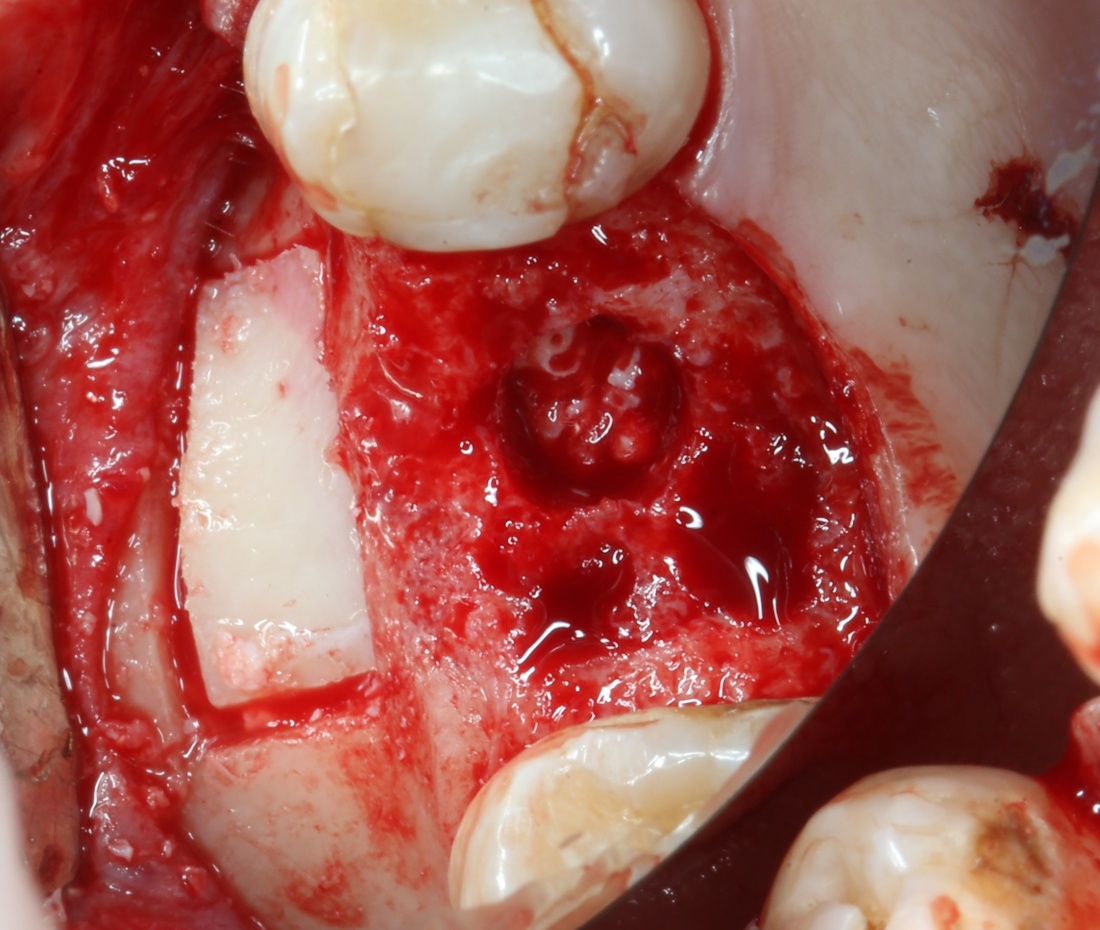

Кортикальная фреза погружается строго до отметки (см выше). В нашем клиническом случае (с синуслифтингом) это особенно важно, чтобы имплантат не улетел в субантральное пространство. Таким образом получаем лунку, полностью конгруэнтную будущему имплантату. Это очень-очень важно:

Пришло время вернуться к синуслифтингу и заполнить сформированное ранее субантральное пространство графтом (Geistlich Bio-Oss Pen):